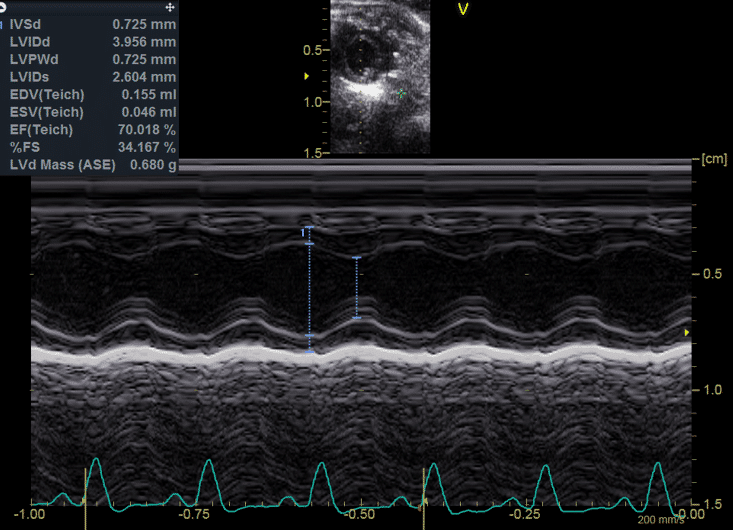

• fonction ventriculaire systolique;

• fonction ventriculaire diastolique;

• analyse des déformations cardiaques (strain).